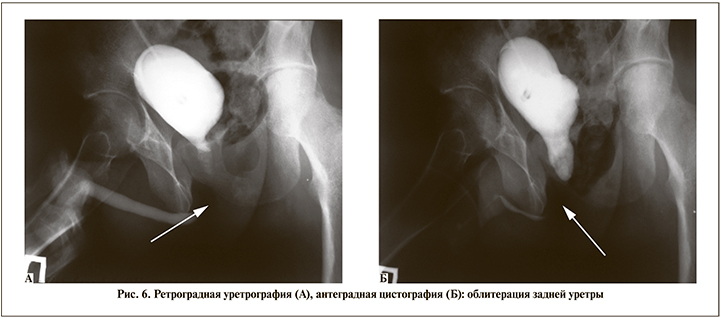

Пострадавший Е. 1992 г.р. В результате ДТП получил травмы: закрытый перелом костей таза, разрыв мембранозного отдела уретры. Находился на лечении в ЦРБ, где выполнена операция по ушиванию разрыва брыжейки тонкой кишки; эпицистостомия. Переведен в «3ЦВКГ им. А. А.Вишневского». По данным ретроградной уретрографии, антеградной цистографии: непреодолимое препятствие (облитерация) в дистальном отделе задней уретры протяженностью до 2 см (рис. 6).

При КТ-исследовании (рис. 7) – облитерация задней уретры на протяжении около 17 мм.

Выполнена операция – анастомотическая уретропластика (операция Хольцова–Мариона). Этапы операции представлены на рис. 8–13. Результат операции представлен на рис. 14. На 15-е сутки удален уретральный катетер, «закрыт» цистостомический свищ. Восстановлено самостоятельное мочеиспускание.